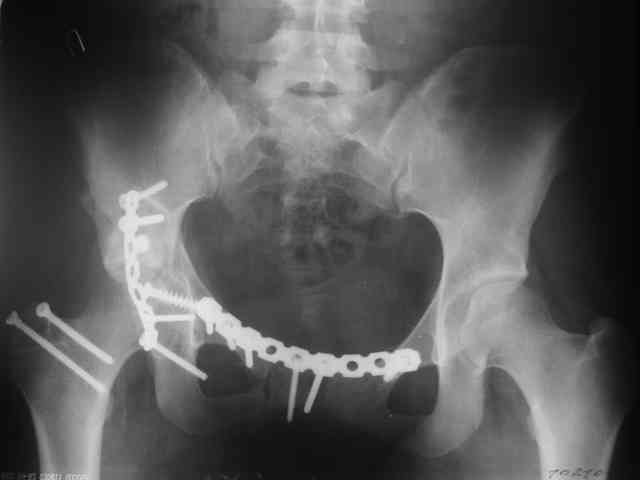

Дальше как обычно: рекон пластнина на заднюю колонну. Устранить смещение передней колонны из заднего доступа оказалось невозможным, пришлось

перевернуть больную на спину и из подвздошного доступа вернуть переднюю колонну на место. Другая проблема возникла с фиксацией лонной кости,

пришлось открывать ся над лобком и ретроградно двумя винтами фиксировать обе ветви лобковой кости справа и слева.

Пока всё ОК снимки сделали сегодня, но пока не сфотографировал В целом суставная поверхность конгруэнтна , по колоннам тоже вроде все ОК.

Интраопер под ЭОПом контролировал направление лонного винта - была абсолютная уверенность в правидльности направл, на постоп. снимке винт вылез :-((.

P.S. в приложении R пациентки с похожей проблемой доступа.. за исключением того, что перелом

двухколонный. Вертлугу лечили Y доступом.